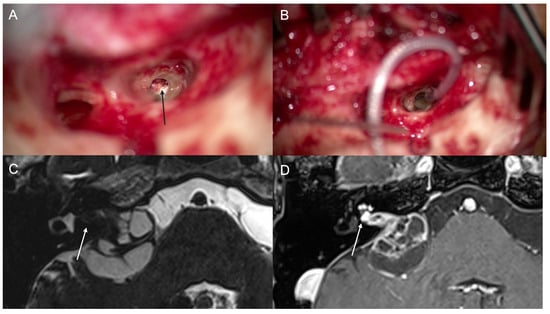

3.3. Case 3